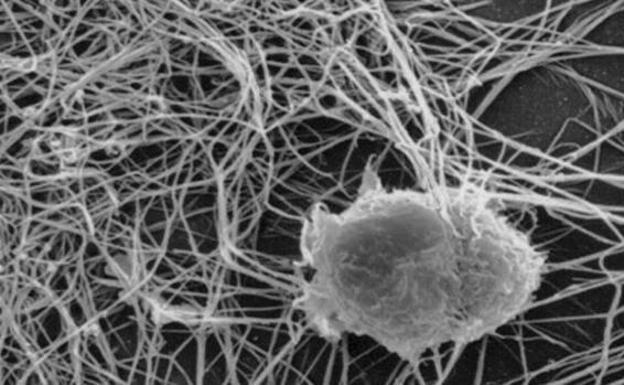

Reducir al mínimo tabaco, alcohol y obesidad y extender la detección precoz evitaría 55.000 muertes cada año y rebajaría a casi la mitad la factura de esta patología